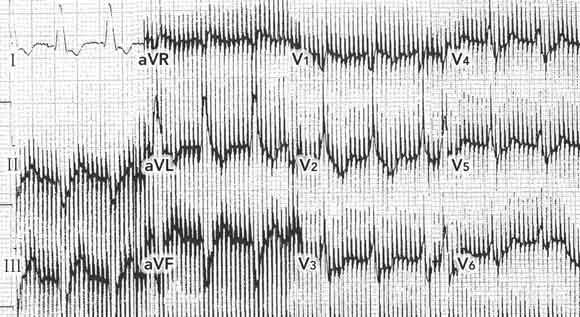

A 74-year-old woman presented to hospital with dyspnoea of sudden onset. She was in cardiogenic shock, with blood pressure of 90/50 mmHg, and pulse rate of 115 bpm. The electrocardiogram (ECG) was difficult to interpret because of severe, persistent and inexplicable artefacts (Box 1A). Chest x-ray showed acute pulmonary oedema thought secondary to left ventricular failure. Echocardiography showed a left ventricular ejection fraction of 40% and anterior akinesia. Coronary angiography confirmed a proximal occlusion of the left anterior descending coronary artery, which was successfully treated by direct angioplasty and stenting.

Persistent and inexplicable ECG artefacts should raise the suspicion of interference from a device generating high frequency electrical impulses. Such devices may include minute ventilation rate-responsive pacemakers1 and central or transcutaneous neurostimulators (eg, deep brain neurostimulators used in Parkinson’s disease,2 and spinal neurostimulators used in chronic back pain3). Occasionally, when the vector of impulses is perpendicular to an ECG lead, the tracing from that lead may be free of artefacts (eg,Box 1A, lead I).

Intrathoracic devices are usually discovered on physical examination or standard chest x-ray, but devices in other parts of the body may not be obvious. In dynamic graciloplasty to treat anal incontinence, the gracilis muscle is transposed around the anal canal and electronically stimulated by a device placed in a subcutaneous pocket in the abdominal wall.4 In our case, this device led to ECG artefacts potentially interfering with the ability to diagnose the acute myocardial infarction.